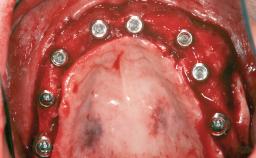

Bone Augmentation Staged|Vertical

Augmentation Materials Autogenous chips|Membrane

Bone Volume Deficient vertically or deficient vertically AND horizontally